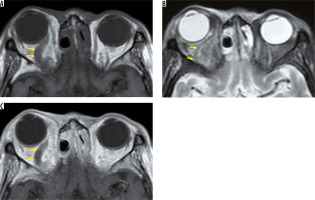

Figure 16

Lymphoma. An ill-defined low-signal mass (yellow arrows) is located around the left optic nerve on the T1-weighted image (A). The mass has low signal on the STIR image (B) and contrast effect on the post-contrast, fat-suppressed, T1-weighted image (C)